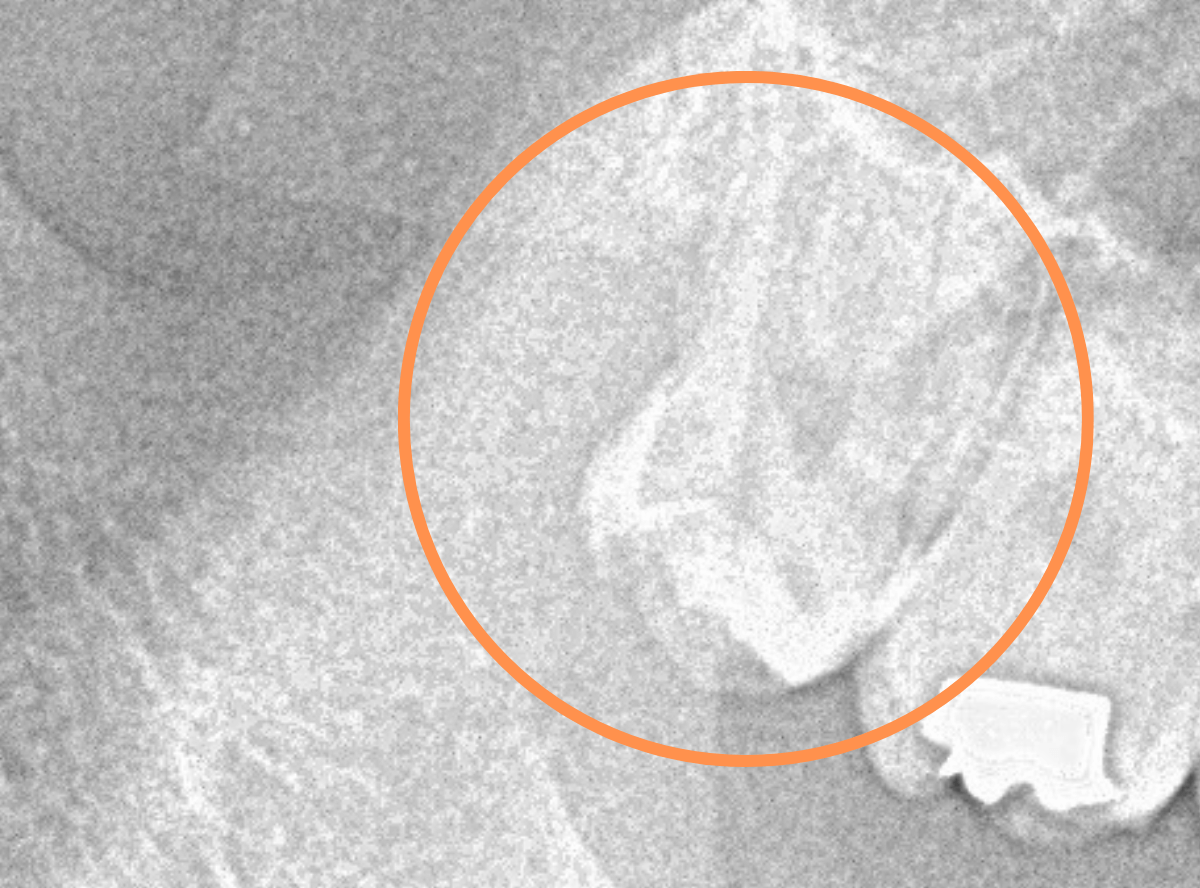

このようなおやしらず、あなたはありませんか?